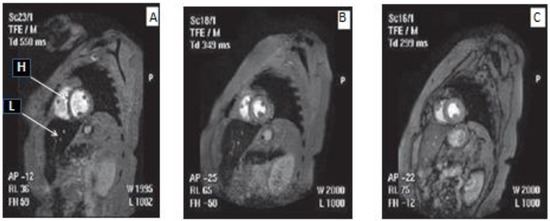

- Kolnagou, A.; Yazman, D.; Economides, C.; Eracleous, E.; Kontoghiorghes, G.J. Uses and Limitations of Serum Ferritin, Magnetic Resonance Imaging T2 and T2* in the Diagnosis of Iron Overload and in the Ferrikinetics of Normalization of the Iron Stores in Thalassemia Using the International Committee on Chelation Deferiprone/Deferoxamine Combination Protocol. Hemoglobin 2009, 33, 312–322. [Google Scholar] [CrossRef] [PubMed]

- Mavrogeni, S.I.; Gotsis, E.D.; Markussis, V.; Tsekos, N.; Politis, C.; Vretou, E.; Kermastinos, D. T2 relaxation time study of iron overload in b-thalassemia. Magn. Reson. Mater. Phys. Biol. Med. 1998, 6, 7–12. [Google Scholar] [CrossRef] [PubMed]

- Anderson, L.; Holden, S.; Davis, B.; Prescott, E.; Charrier, C.; Bunce, N.; Firmin, D.; Wonke, B.; Porter, J.; Walker, J.; et al. Cardiovascular T2-star (T2*) magnetic resonance for the early diagnosis of myocardial iron overload. Eur. Hear. J. 2001, 22, 2171–2179. [Google Scholar] [CrossRef] [PubMed]

- Pennell, D.J. T2* Magnetic Resonance and Myocardial Iron in Thalassemia. Ann. N. Y. Acad. Sci. 2005, 1054, 373–378. [Google Scholar] [CrossRef]

- Wood, J.C. Diagnosis and management of transfusion iron overload: The role of imaging. Am. J. Hematol. 2007, 82, 1132–1135. [Google Scholar] [CrossRef] [PubMed]